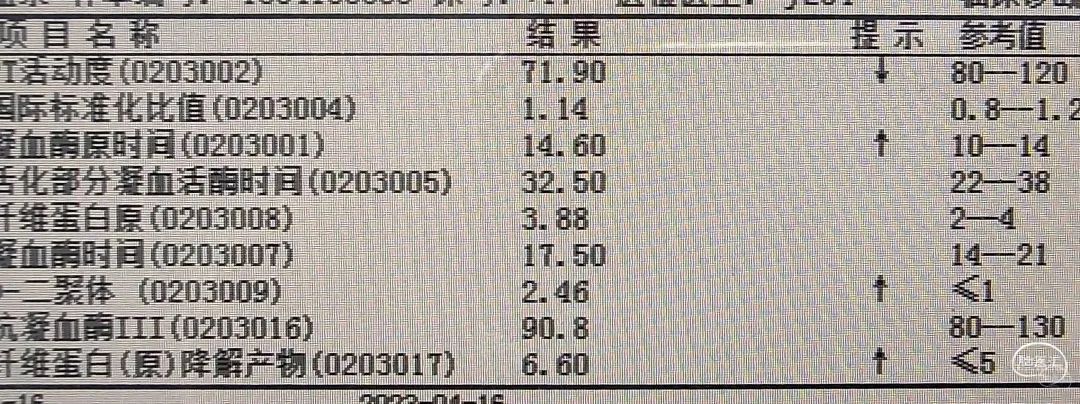

术前化验

术前化验